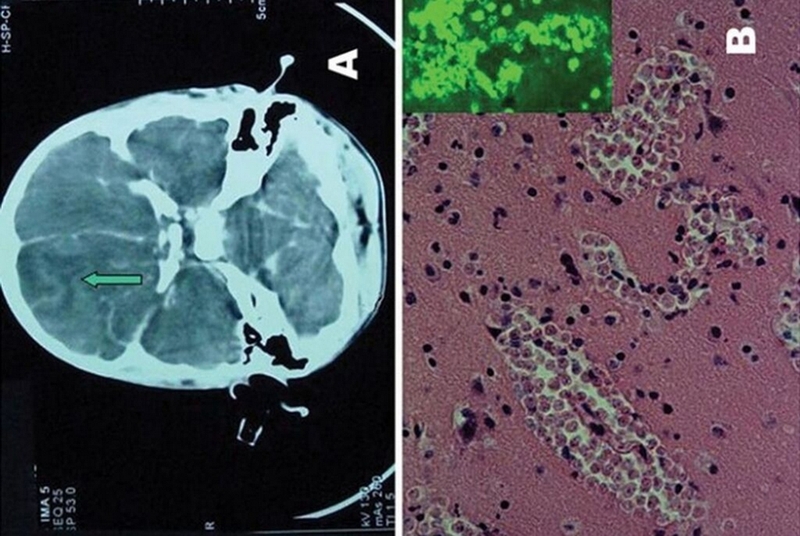

Bệnh amip ăn não có thể được chẩn đoán bằng chụp cắt lớp vi tính (hay còn gọi là CT) hoặc chụp cộng hưởng từ ( chụp MRI), bởi 2 phương pháp này có thể nhìn thấy được vết sưng và chảy máu bên trong não:

Ngoài ra, amip ăn não cũng có thể được chẩn đoán bằng cách chọc dò tủy sống bởi Naegleria fowleri có thể được nhìn thấy dưới kính hiển vi ở phương pháp này. Bác sĩ sẽ tiến hành chọc hút dịch não tủy ở vị trí đốt sống L2 - S2. Trong quá trình chọc hút này, bác sĩ cũng sẽ đồng thời đo áp lực dịch não tủy để đánh giá xem liệu người bệnh có tăng áp lực nội sọ hay không.